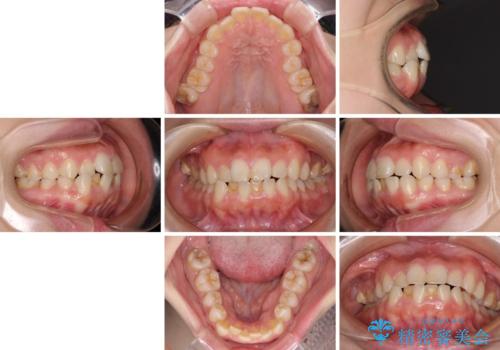

- 前歯が突出しているために口が閉じられないとのことで来院された患者様です。

上下ともに顎が小さく、歯列が前方に突き出していたため、上下左右の第一小臼歯4本を抜歯し、口元の突出感を改善していくこととしました。